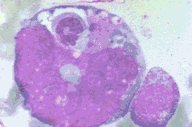

Megakaryocyte showing emperipolesis

This low oil magnification view of a more mature

megakaryocyte with some lobulation also shows

an engulfed but undamaged neutrophil and an

engulfed but undamaged erythrocyte. This is

referred to as empiripolesis.